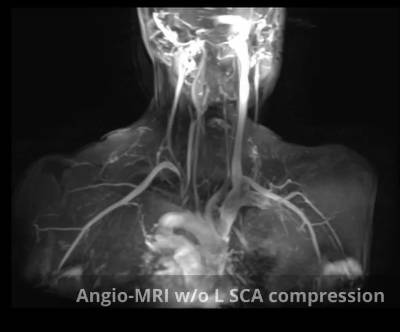

Per realitzar un diagnòstic precís es requereixen les proves següents:

- AngioTAC Cervico-toràcic/Angio RM cervico-toràcica amb maniobres de compressió